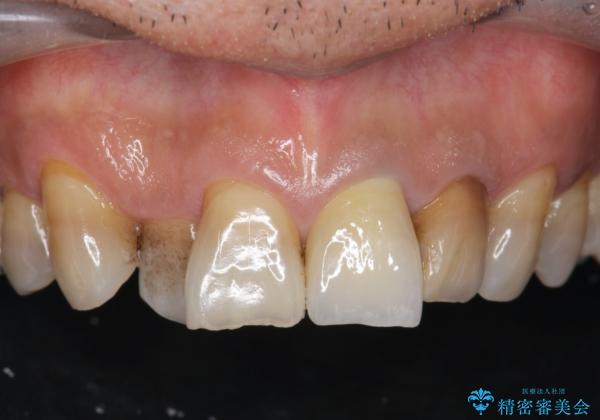

[前歯 セラミック治療] すぐに前歯が取れる きちんと治療して欲しい

- 他院で前歯の治療を繰り返し行うものの、クラウン・コアの脱離が頻回に起きやり直しのない治療を求めて来院されました。

脱離により感染のうかがわれる根管内は再根管治療を行い、ラバーダムを行い防湿下でファイバーコア築盛を行うことで脱離への抵抗性を高めます。

歯肉縁上の歯質が少ない場合脱離や破折リスクが高まるためコアの丁寧な築盛や綿密な咬合調整が必要です。